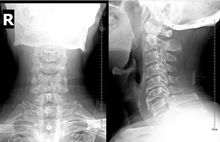

頸椎強直是頸椎病的一種,也是頸椎生理曲度變直。由於頸椎及頸部軟組織慢性損傷或退變引起脊柱內外力學平衡失調,壓迫或刺激頸部血管、神經和脊髓引起頭、頸、肩臂、上肢、背中部、胸部疼痛及其它症狀,甚至合併肢體功能障礙等一組臨床症候群。病症輕者頭痛、頭暈、噁心嘔吐、頸肩疼痛、上肢麻木、無力、耳鳴、視物模糊、胸悶心慌等,重者還可導致肢體癱瘓、大小便障礙,甚至危及生命。對一般人來說,每天至少有1/4~1/3時間是在睡眠中度過,因此,如果枕頭使用不當或不用枕頭,容易引起或加劇頸椎強直。反之,如果注意和調整頸椎在睡眠中的姿勢,亦可有預防和治療作用。睡眠時枕頭是維持頭頸正常位置即生理曲度的重要工具,這種生理曲線既是頸椎外在肌群平衡的保證,又是保持頸椎管內生理結構狀態不可缺少的條件。如果枕頭選擇和使用不當,不僅破壞了維持頸椎正常弧度的外在平衡,而且也直接影響頸椎管內容積的大小和局部組織的生理結構。因此,枕頭的高低必需引起高度重視。

頸椎的生理曲度(簡稱頸曲)並非是一成不變的。隨著年齡的增長、頸椎會出現退行性改變、頸椎骨質增生、從而使頸曲發生改變,甚至使頸曲變直或反張彎曲。再有,當人們長期姿勢不當、生活習慣不良,比如長時間低頭工作、睡高枕或頸部外傷、外感風寒時,頸椎的生理曲度也容易發生改變。頸曲的改變或消失,往往意味著椎體穩定性變差,椎間隙變窄,椎間孔變小,椎體退變,神經受壓以及頸伸肌慢性損傷。另外,頸曲的消失也會導致黃韌帶肥厚、頸韌帶損傷、椎體旁有關肌肉的損傷等,進而誘發頸椎病變。這時,人很有可能出現頭頸肩背疼痛或感覺麻木無力,甚至出現大小便失禁、癱瘓等一系列頸椎綜合症,所以頸椎病的治療要從平時的日常生活中積極地治療預防,建議多關注一些醫療器械類的有治療作用的,如對於頸部鎮痛的、幫助睡眠的又安眠作用的,一些常用的合適的枕,它根據人體的頸部正常生理曲度設計,對於頸椎病的治療和恢復有重大的意義。